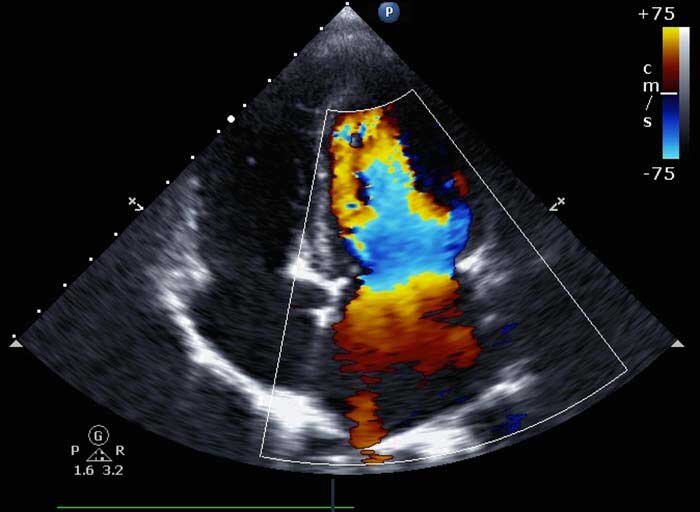

مدیر بخش تصویربرداری پژوهشگاه رویان درباره سونوگرافی هایی که روند مراقبت از جنین در رحم مادر را کامل می کند توضیح می دهد: «چند سونوگرافی اختصاصی هست که در موارد خاص استفاده می‌شود. مثل سونوگرافی بیوفیزیکال که تنفس، حرکت و حجم مایع را به صورت اختصاصی بررسی می‌کند؛ برای مادرانی که دیابتی هستند یا جنین آنها درریسک خطرهای خاصی قرار دارد استفاده می‌شود. نوع دیگر سونوگرافی تکمیلی در بارداری، سونوگرافی رنگی(کالرداپلر) است که بعضی اوقات برای بررسی چسبندگی‌های جفت استفاده می‌شود؛ خصوصا در بانوانی که سابقه سزارین داشته‌اند(از عوارض سزارین، چسبندگی‌های جفت است). همچنین در مواقعی که جنین رشد مناسبی ندارد، برای این که علت را مشخص کنند اولین اقدامی که انجام می‌شود، بررسی وضعیت خون‌رسانی جنین با استفاده از سونوگرافی داپلر است.